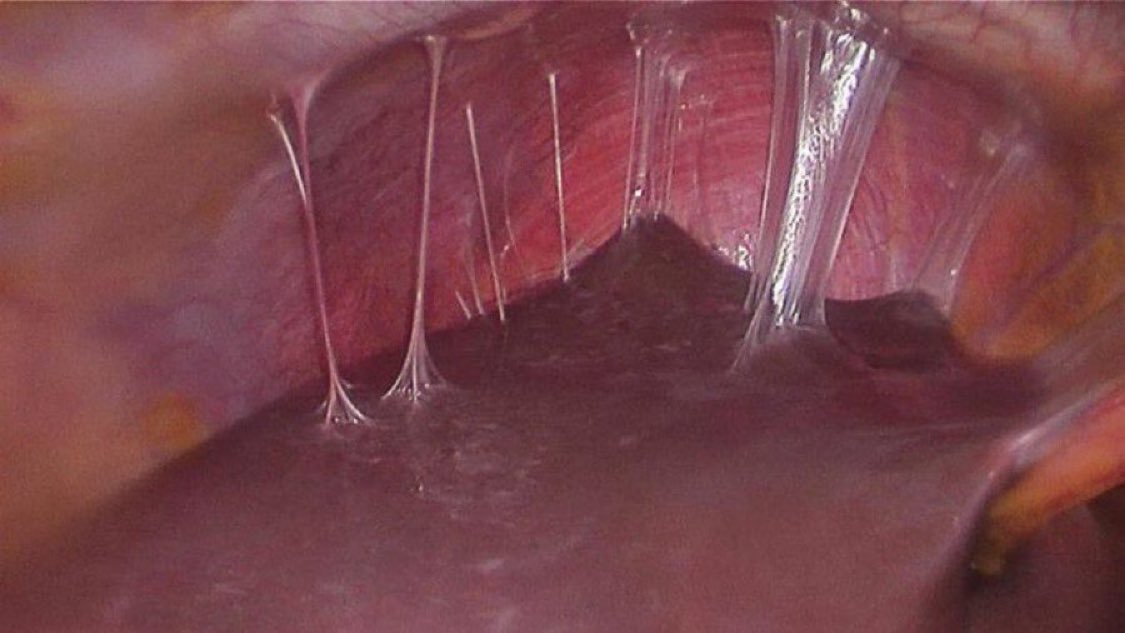

la CANTIDAD de estos que vi rotando por cirugía yo pensaba que era una rareza pregunta de examen de bacterio no más

Appearance of the liver during laparoscopy in a patient with chronic abdominal pain. What’s the diagnosis?

TrackYourHeart's tweet image. Appearance of the liver during laparoscopy in a patient with chronic abdominal pain. What’s the diagnosis?